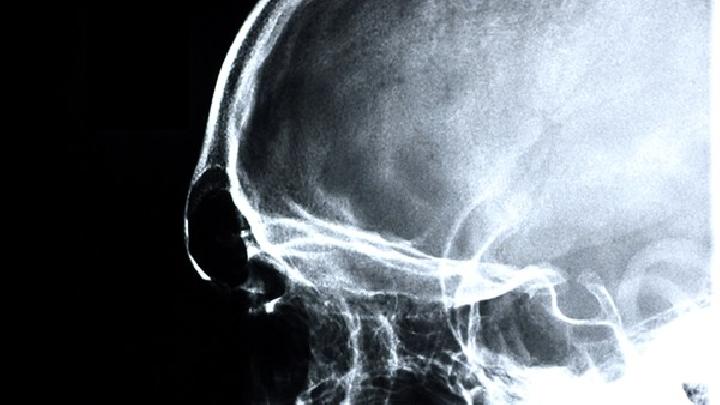

脑胶质瘤(脑胶质细胞瘤)约占颅内肿瘤的比例46%,据1996年第三届(悉尼)国际肿瘤控制大会统计,脑胶质瘤发病率为3~10万,占全身恶性肿瘤的比例1%~3%,平均生存期仅为8~11个月。脑肿瘤中胶质细胞瘤发病率最高,综合发病年龄高峰为 30-40岁,或10-20岁。大脑半球发生的胶质瘤约占所有胶质瘤的比例。51.4%,以星形细胞瘤为主,其次是胶质细胞瘤和少枝胶质细胞瘤,脑室系统也是胶质瘤较多的发生部位,占胶质瘤总数的23 .9%,主要为管膜瘤、髓母细胞瘤、星形细胞瘤、小脑胶质瘤占胶质瘤总数13%,主要是星形细胞瘤。